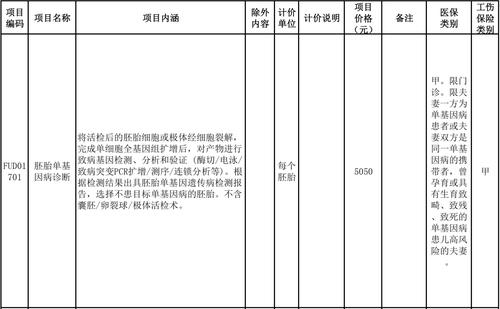

记者注意到,16项纳入医保甲类报销范围的辅助生殖技术的项目价格从180元到五千余元不等,其中价格最高的技术项目为5050元/每个胚胎的胚胎单基因病诊断。项目类型则涵盖人工授精、胚胎的移植与培养等多种服务项目。

价格为5050元的胚胎单基因病诊断项目

图片来源:部分医疗服务价格项目表截图